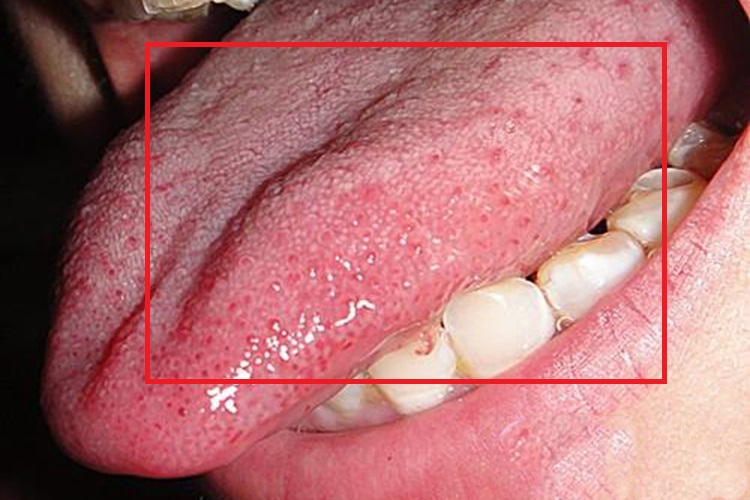

舌头丘疹常见于舌乳头炎,可分为丝状乳头炎、菌状乳头炎、轮廓乳头炎、叶状乳头炎,具体的症状表现有所不同。

丝状乳头炎:主要表现为舌背丝状乳头萎缩,舌黏膜充血发红,像舌头长丘疹一样。

菌状乳头炎:分布于丝状乳头之间的菌状乳头表现为充血水肿、肿胀和红色病损,点状分布呈草莓状,看着像舌头丘疹,灼痛明显。

轮廓乳头炎:轮廓乳头于舌后1/3处,一般7-9个,呈人字形排列,其侧壁上皮内含味蕾。炎症时乳头肿大突起,出现舌头丘疹,轮廓清晰且发红,疼痛感不明显,还可伴有味觉迟钝等症状。

叶状乳头炎:叶状乳头位于舌缘后部,靠近咽部,为5-8条上下并列皱襞。存在炎症时乳头红肿,像丘疹一样,乳头间皱更显凹陷,患者常有明显的刺激痛或不适感。